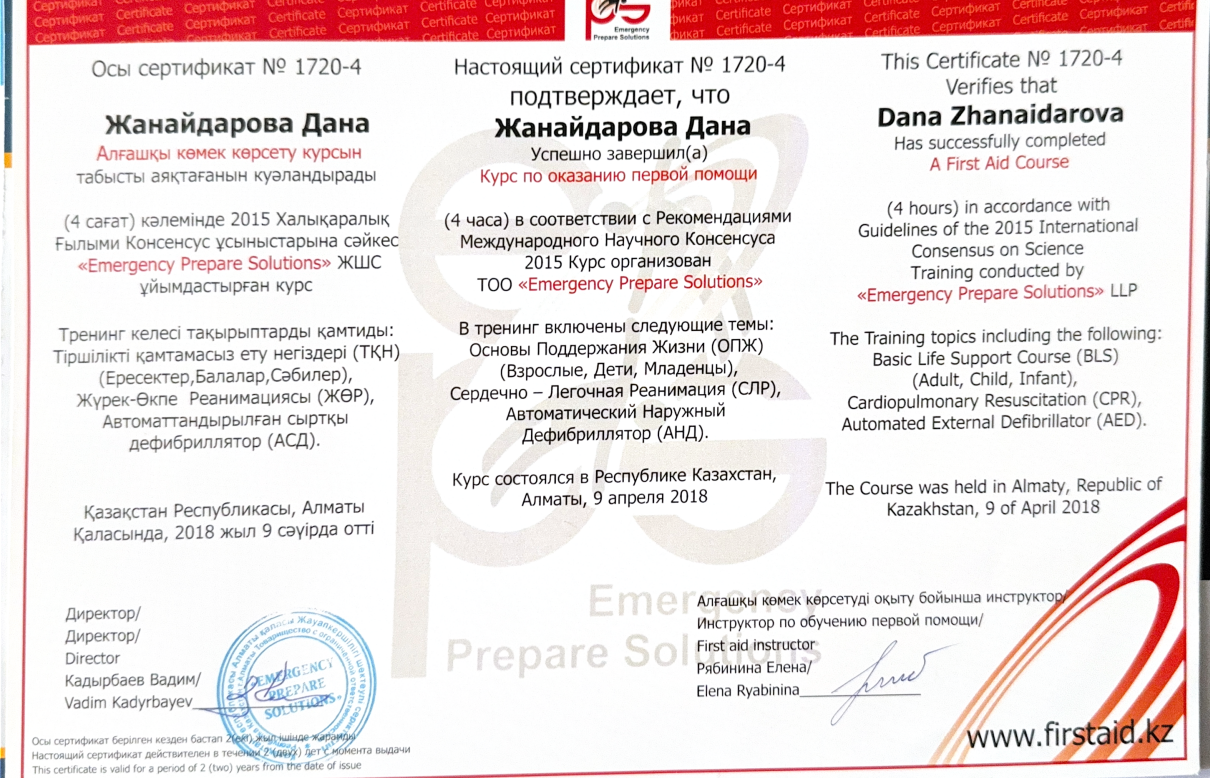

Регулярно совершенствует знания в стоматологии